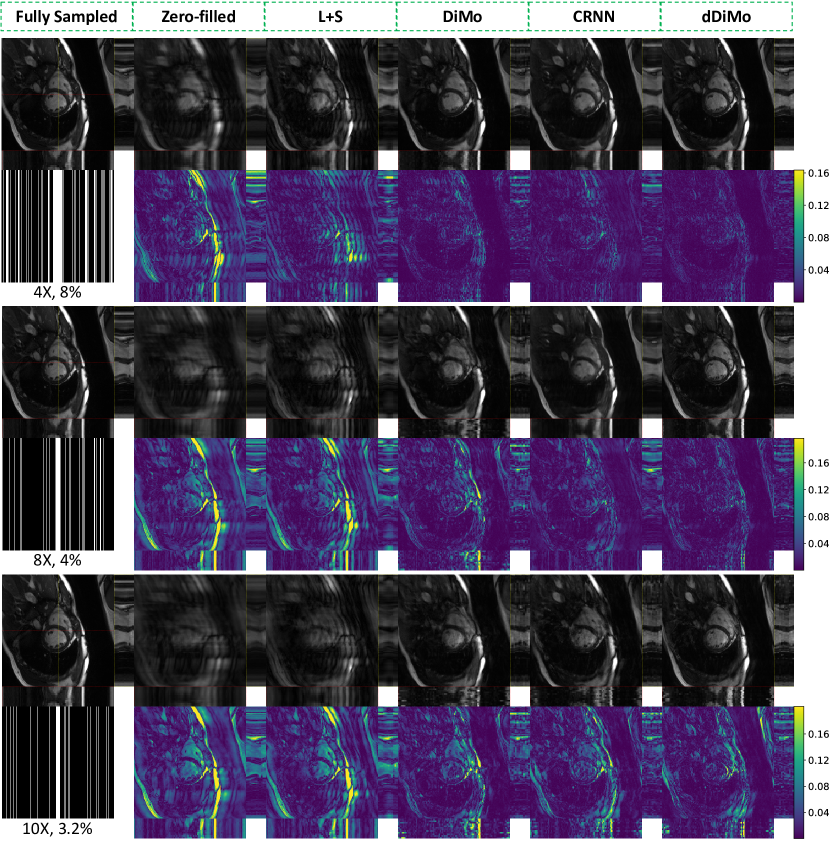

4.1 Results of Cardiac Cine

Exemplary reconstructions from various methods for cine images at different acceleration factors and cardiac views are shown in Figure 4, Figure 5, and Supporting Information Figure S1 and Figure S2. The proposed dDiMo method demonstrates superior performance in artifact suppression, detail preservation, and accurate cardiac motion capture, producing sharp and clear reconstructions. In contrast, competing methods, including L+S, DiMo, and CRNN, exhibit notable artifacts, spatial blurring, and temporal misalignment, particularly at higher acceleration factors. Exemplary - profiles extracted along the vertical yellow dashed line and horizontal red dashed line, as indicated by the yellow and red dashed rectangles on the spatial reconstruction images, are presented to illustrate temporal alignment across cardiac frames. Reconstructions from dDiMo achieve better alignment along the cardiac phase, with clearer boundary definitions that closely resemble the fully sampled reference image compared to other methods. These observations are further supported by error maps of the reconstructed spatial images and - profiles. Zero-filled reconstructions show the largest errors, followed by L+S, DiMo, and CRNN. In general, CRNN shows improved performance over DiMo by leveraging temporal characterization, while DiMo, which processes each frame independently, results in misaligned cardiac phases due to the lack of temporal information integration during the diffusion process.

Quantitative results for SAX and LAX views of cine reconstruction are summarized in Table 1. Metrics such as PSNR, SSIM, NMSE, and Tenengrad confirm that dDiMo consistently outperforms baseline methods in acceleration factors (4, 8, and 10) and cardiac views. Even at higher acceleration rates, where reconstruction becomes more challenging, dDiMo demonstrates superior performance across all metrics, highlighting its robustness. Violin plots in Figure 6 provide a visual comparison of the distributions of PSNR, SSIM, NMSE, and Tenengrad metrics for different acceleration settings. dDiMo achieves the highest median values for PSNR, SSIM, and Tenengrad and the lowest NMSE, with minimal variability and fewer outliers. This demonstrates its ability to produce stable and reliable reconstructions under challenging conditions. These quantitative results validate the qualitative findings and confirm the effectiveness of dDiMo for Cartesian-acquired dynamic MRI reconstruction.